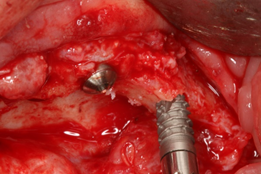

Para a realização da ROG, utilizou-se a técnica Barbell Technique6 (Figura 3), com um enxerto composto por osso autógeno particulado e substituto ósseo mineral inorgânico de origem bovina Bio-Oss (Geistlich) na proporção 1:1, coberto por uma membrana de colágeno reabsorvível Bio-Gide (Geistlich).

O implante Maestro tem se demonstrado como uma excelente opção em pacientes com baixa qualidade óssea, como também em regiões onde foram realizados procedimentos de enxertia óssea. Para a reabilitação desse caso clínico específico, os implantes Maestro Cone Morse e HI foram escolhidos devido às suas características diferenciadas de macrogeometria, aliadas ao seu tratamento de superfície. As câmaras de cicatrização incorporadas na macrogeometria dos implantes Maestro apresentam uma evidente aceleração no processo de osseointegração, bem como na qualidade desse processo 7,8. O design do implante favorece sua inserção com baixo torque, o que é essencial em regiões enxertadas. Os implantes foram instalados com torques de travamento primário variando entre 10 e 25 N (Figuras 5 a 8).